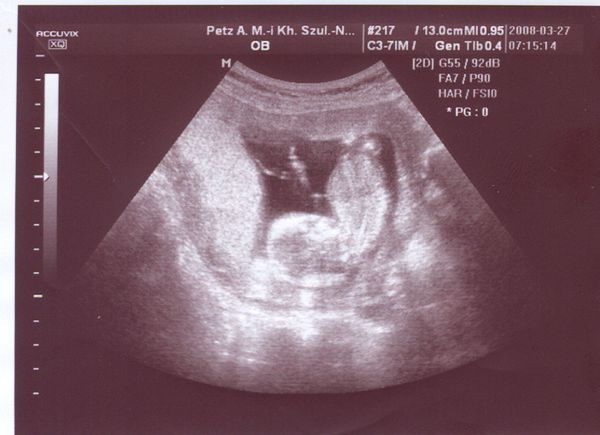

alszik

alszik